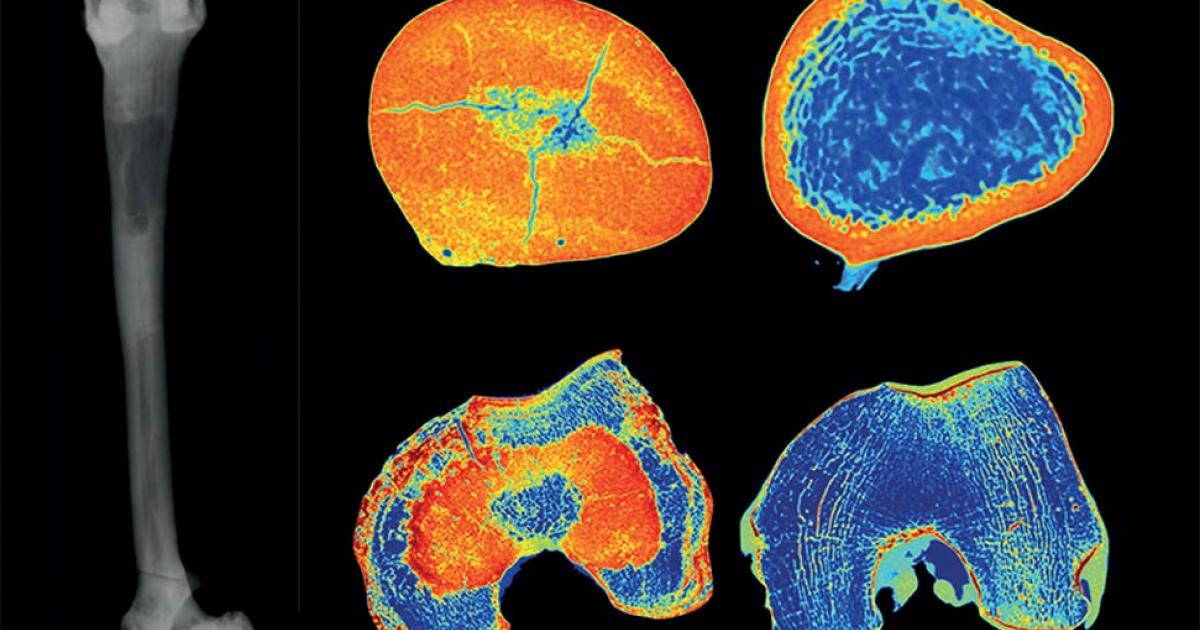

An examination of the bones using X-rays, CT scans and under the microscope revealed that the man had clear signs of having the genetic disorder commonly called stone bone disease and known to medical professionals as osteopetrosis. The Mail Online reports that these signs include “the bones all being unusually heavy and featuring evidence of tissue stiffening, obliteration of the marrow cavity and distinct flaring of the 'neck sections' of the long bones.”

Paleontologists analyzing the remains of a Neolithic man unearthed in Maliq, Albania, have discovered that he suffered from a condition known as osteopetrosis, also known as stone bone disease. (Gresky et al. / The Lancet Diabetes and Endocrinology)

While it is impossible to prove how much this genetic condition would have affected the life of the Neolithic person whose remains were found at Maliq, their analysis does show that he suffered from osteopetrosis, also known as stone bone disease. (Gresky et al. / The Lancet Diabetes and Endocrinology)

Top image: Research on a 6000-year-old skeleton has revealed the undeniable presence of the rare genetic disorder known as stone bone disease or osteopetrosis. Left: Left femur in an X-ray. Right: CT scan slices of the same femur (center) are compared with those of a healthy individual (far right). Sourse: Gresky et al. / The Lancet Diabetes and Endocrinology